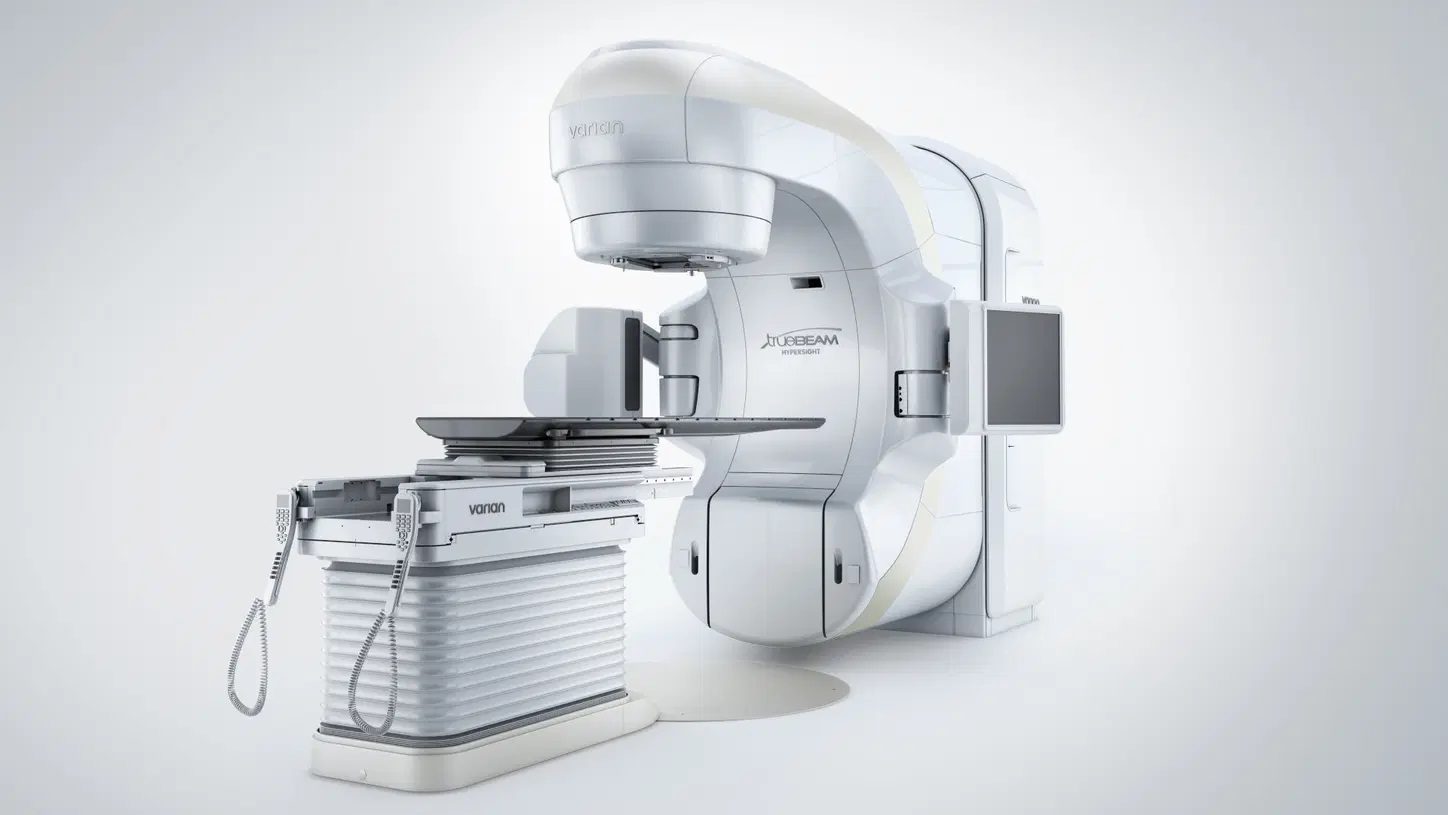

Butterfly Network secures EU MDR certification for Butterfly IQ+ products

Digital ultrasound company Butterfly Network has achieved EU MDR certification for the Butterfly IQ+ ultrasound system, allowing the company to release its offerings into the European market, including its AI-enabled software Auto B-Line Counter…